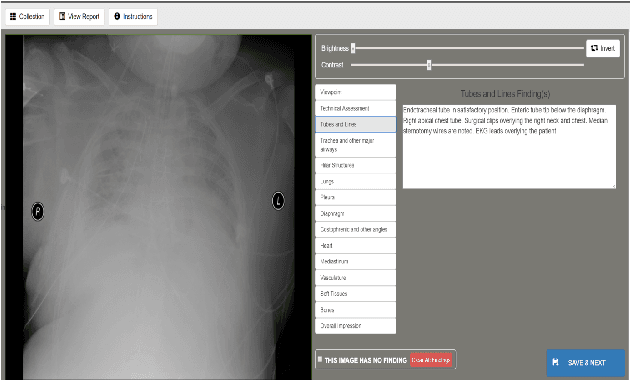

Abstract:Chest X-rays are the most common diagnostic exams in emergency rooms and hospitals. There has been a surge of work on automatic interpretation of chest X-rays using deep learning approaches after the availability of large open source chest X-ray dataset from NIH. However, the labels are not sufficiently rich and descriptive for training classification tools. Further, it does not adequately address the findings seen in Chest X-rays taken in anterior-posterior (AP) view which also depict the placement of devices such as central vascular lines and tubes. In this paper, we present a new chest X-ray benchmark database of 73 rich sentence-level descriptors of findings seen in AP chest X-rays. We describe our method of obtaining these findings through a semi-automated ground truth generation process from crowdsourcing of clinician annotations. We also present results of building classifiers for these findings that show that such higher granularity labels can also be learned through the framework of deep learning classifiers.